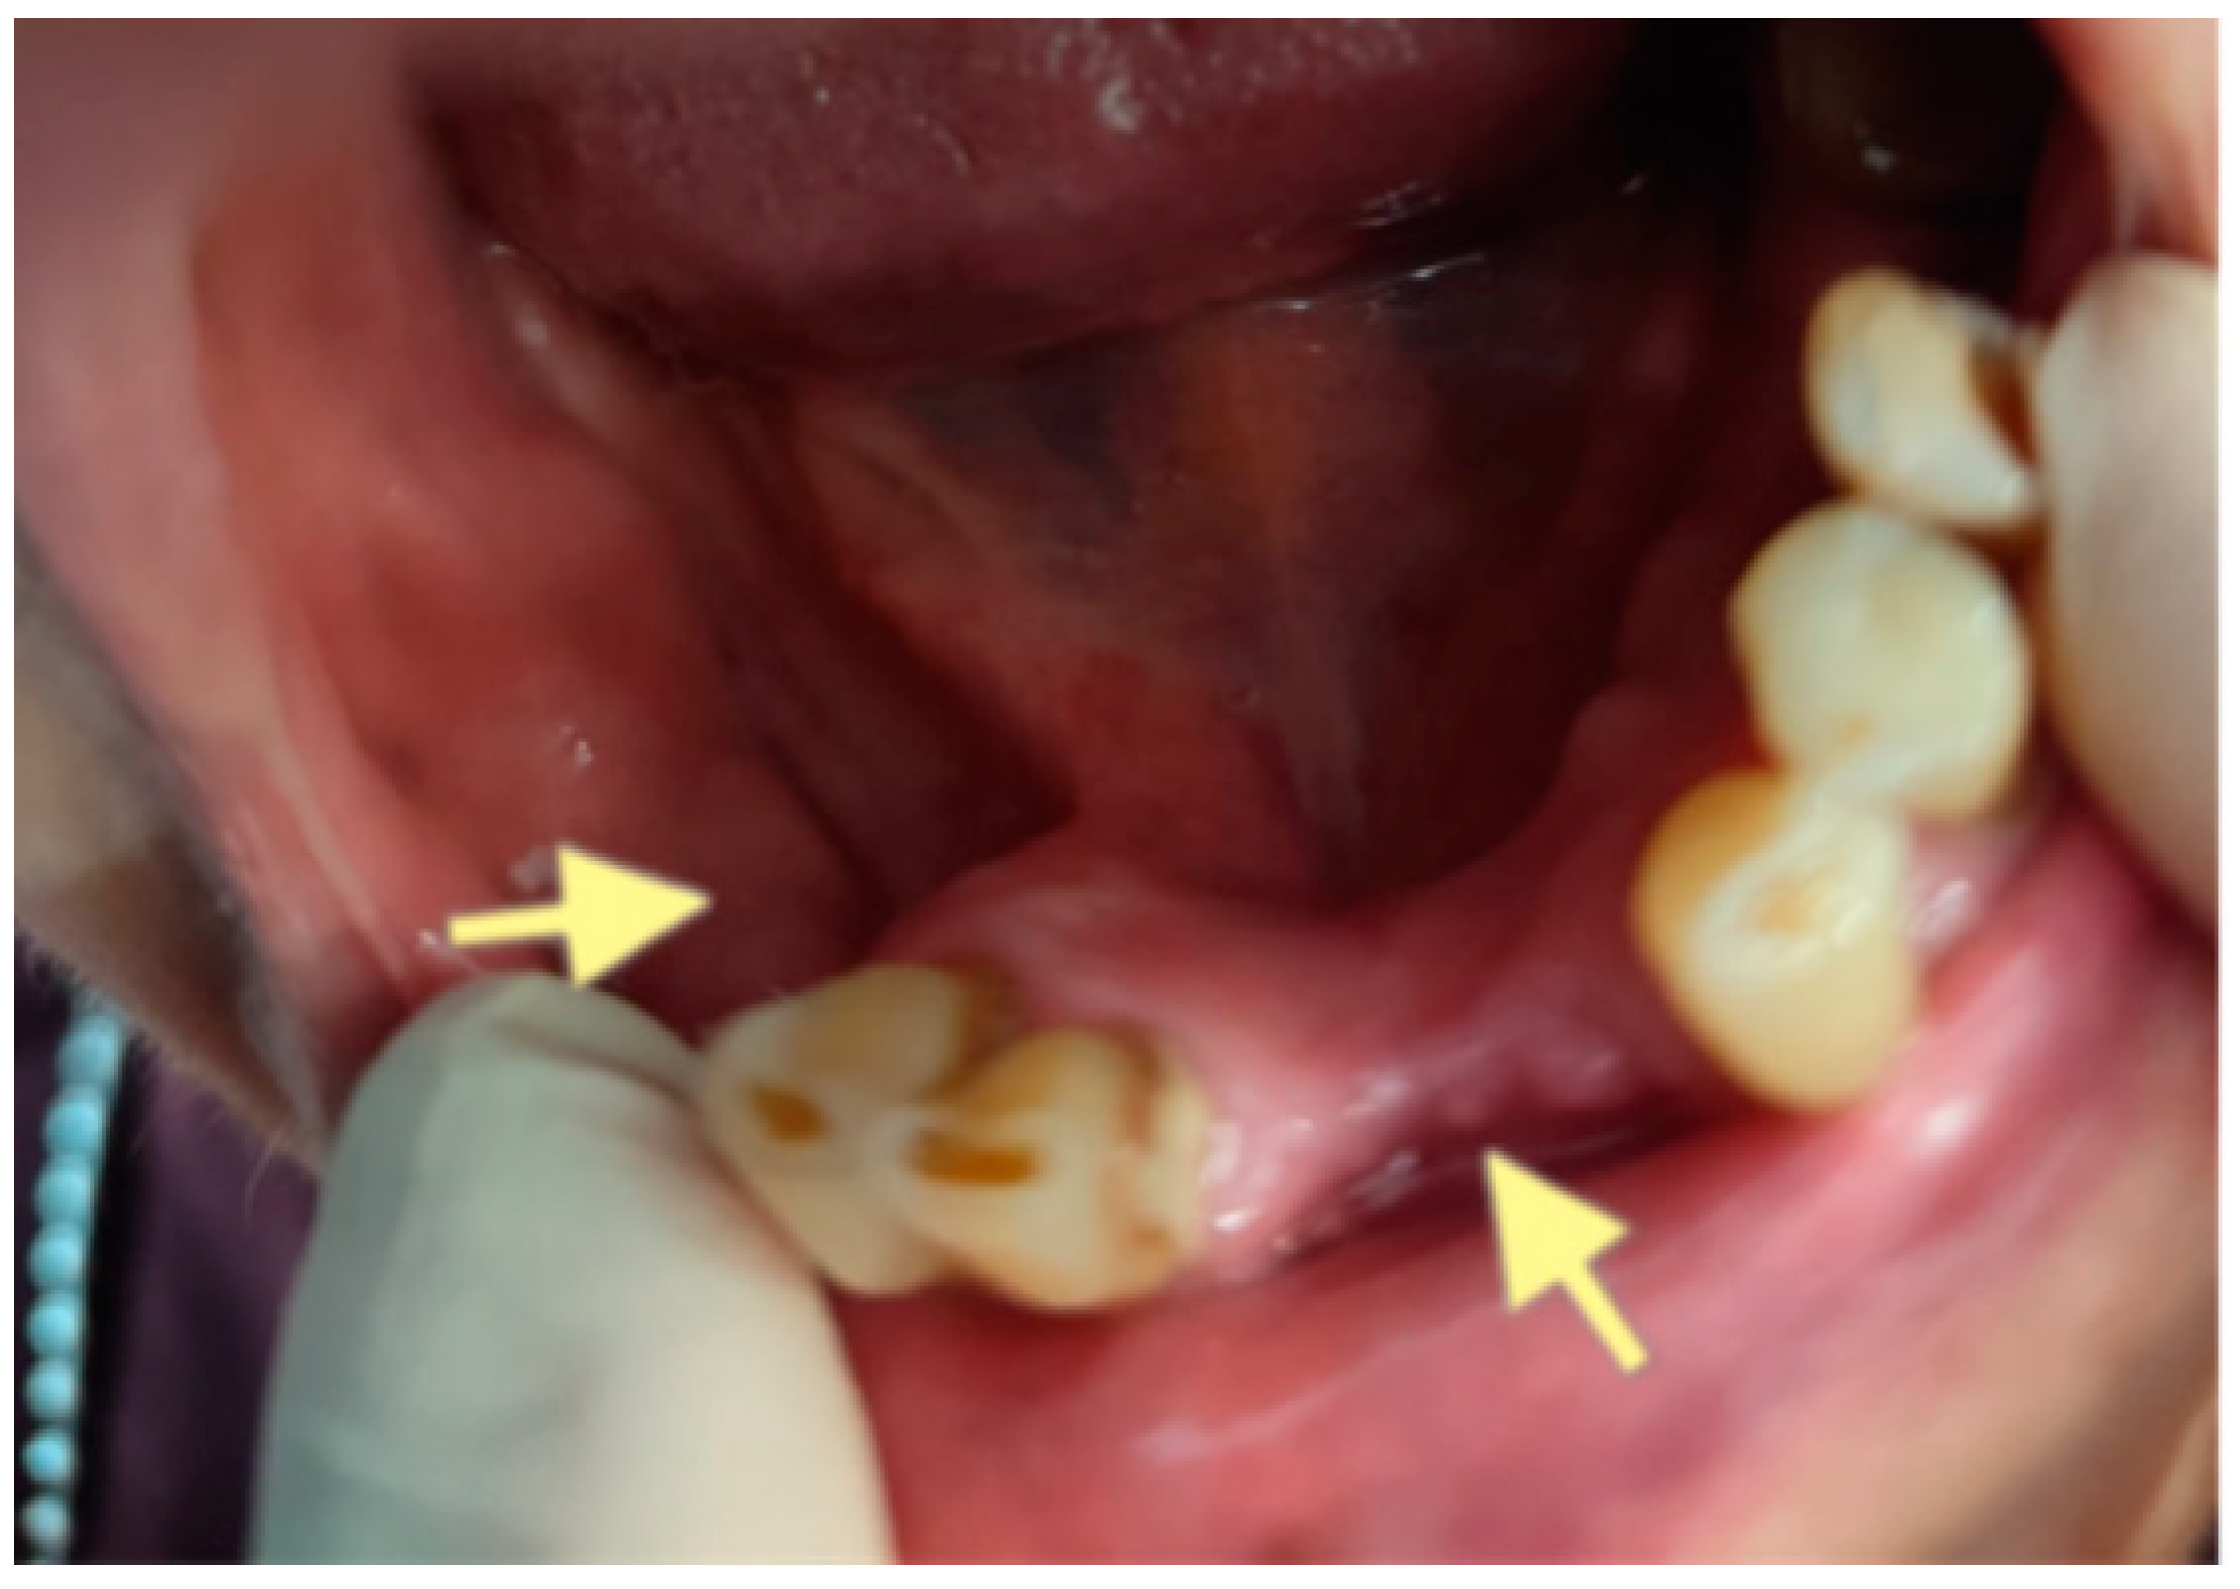

Figure 6.

Control visit of the patient after the second surgery, one month after the second operation performed on 28 May 2025.

However, on 29 September 2025 (last control visit), we noticed complete healing in both areas of the lower jaw. The patient could use a new partial plate for the lower jaw.

The second patient was an 82-year-old female with osteonecrosis of the mandible in the fourth quadrant, which developed after the removal of tooth 46 on November 2023 (see Figure 4). The patient had second-stage osteonecrosis of the jaw. Initially, the patient underwent a revision of the socket of the extracted tooth and was prescribed antibacterial therapy. Despite this treatment, the patient continued to complain of a non-healing wound on the lower jaw in the area of the molars with periodic purulent discharge. In addition, these complaints were supplemented by a complaint of an intraoral fistula on the lower jaw in the area of the frontal teeth. Therefore, in May 2024, the patient underwent surgery (sequestrectomy and application of A-PRF). After the operation, the patient’s condition improved, purulent discharge from the wound stopped, the pain ceased, and the postoperative wound closed completely (see Figure 4). However, after a month, dehiscence of the wound was noted. Therefore, it was decided to repeat the operation, performed on 4 April 2025, and, in addition, to expand the scope of the surgical procedure, the sequestrectomy of the lower jaw was performed not only in the region of dd45-46 but also in the central area, simultaneously applying A-PRF. As a result of the treatment, the surgical wound on the lower jaw in the area of the molars on the right healed completely, but in the area of the incisors, it closed partially (see Figure 5 and Figure 6).